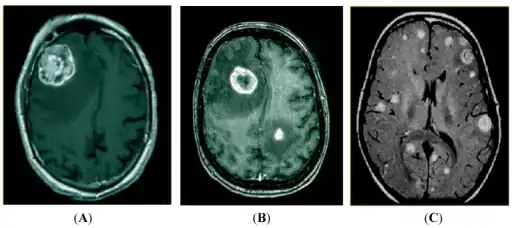

a-c)Magnetic resonance imaging (MRI) detection of brain metastasis -

Brain metastasis in the right cerebral hemisphere from lung cancer shown on T1-weighted magnetic resonance imaging with intravenous contrast.

Brain imaging (neuroimaging such as CT or MRI) is needed to determine the presence of brain metastases.[5] In particular, contrast-enhanced MRI is the best method of diagnosing brain metastases, though detection is primarily done by CT.[9] Biopsy is often recommended to confirm diagnosis.[5]